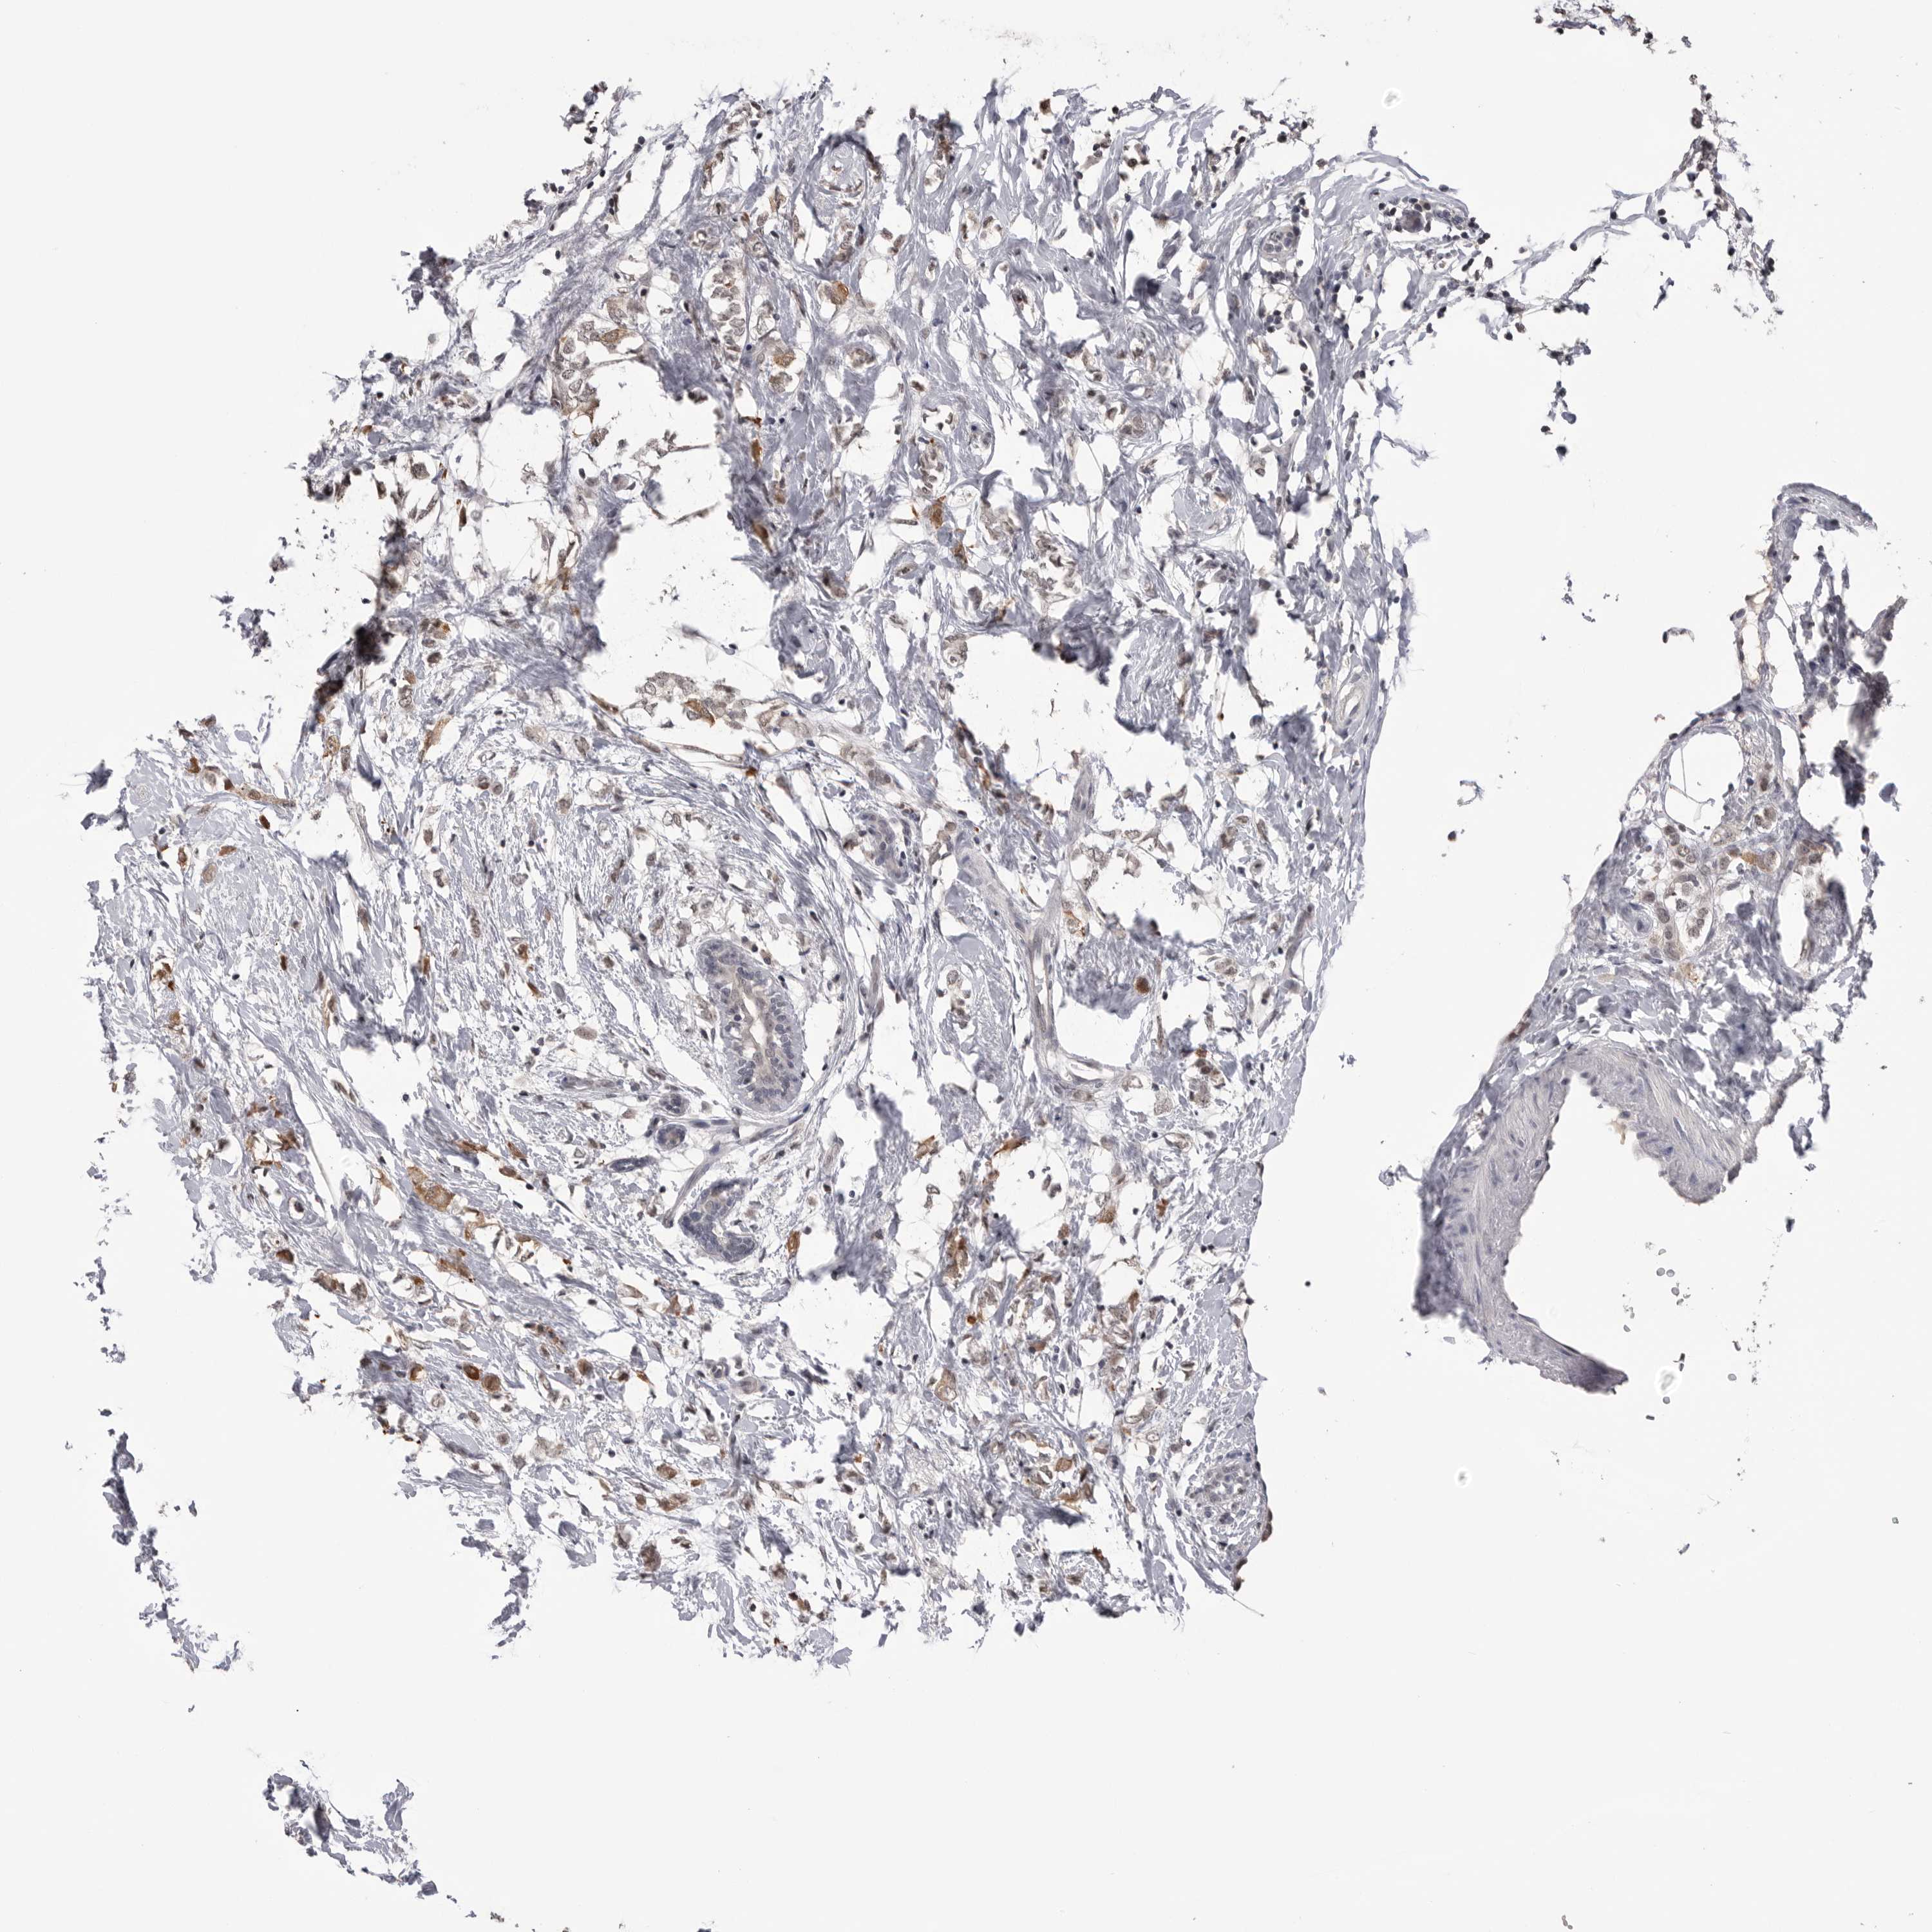

CANCER BREAST CANCER Show tissue menu

BRCA TCGA BRCA VALIDATION PROTEIN EXPRESSION